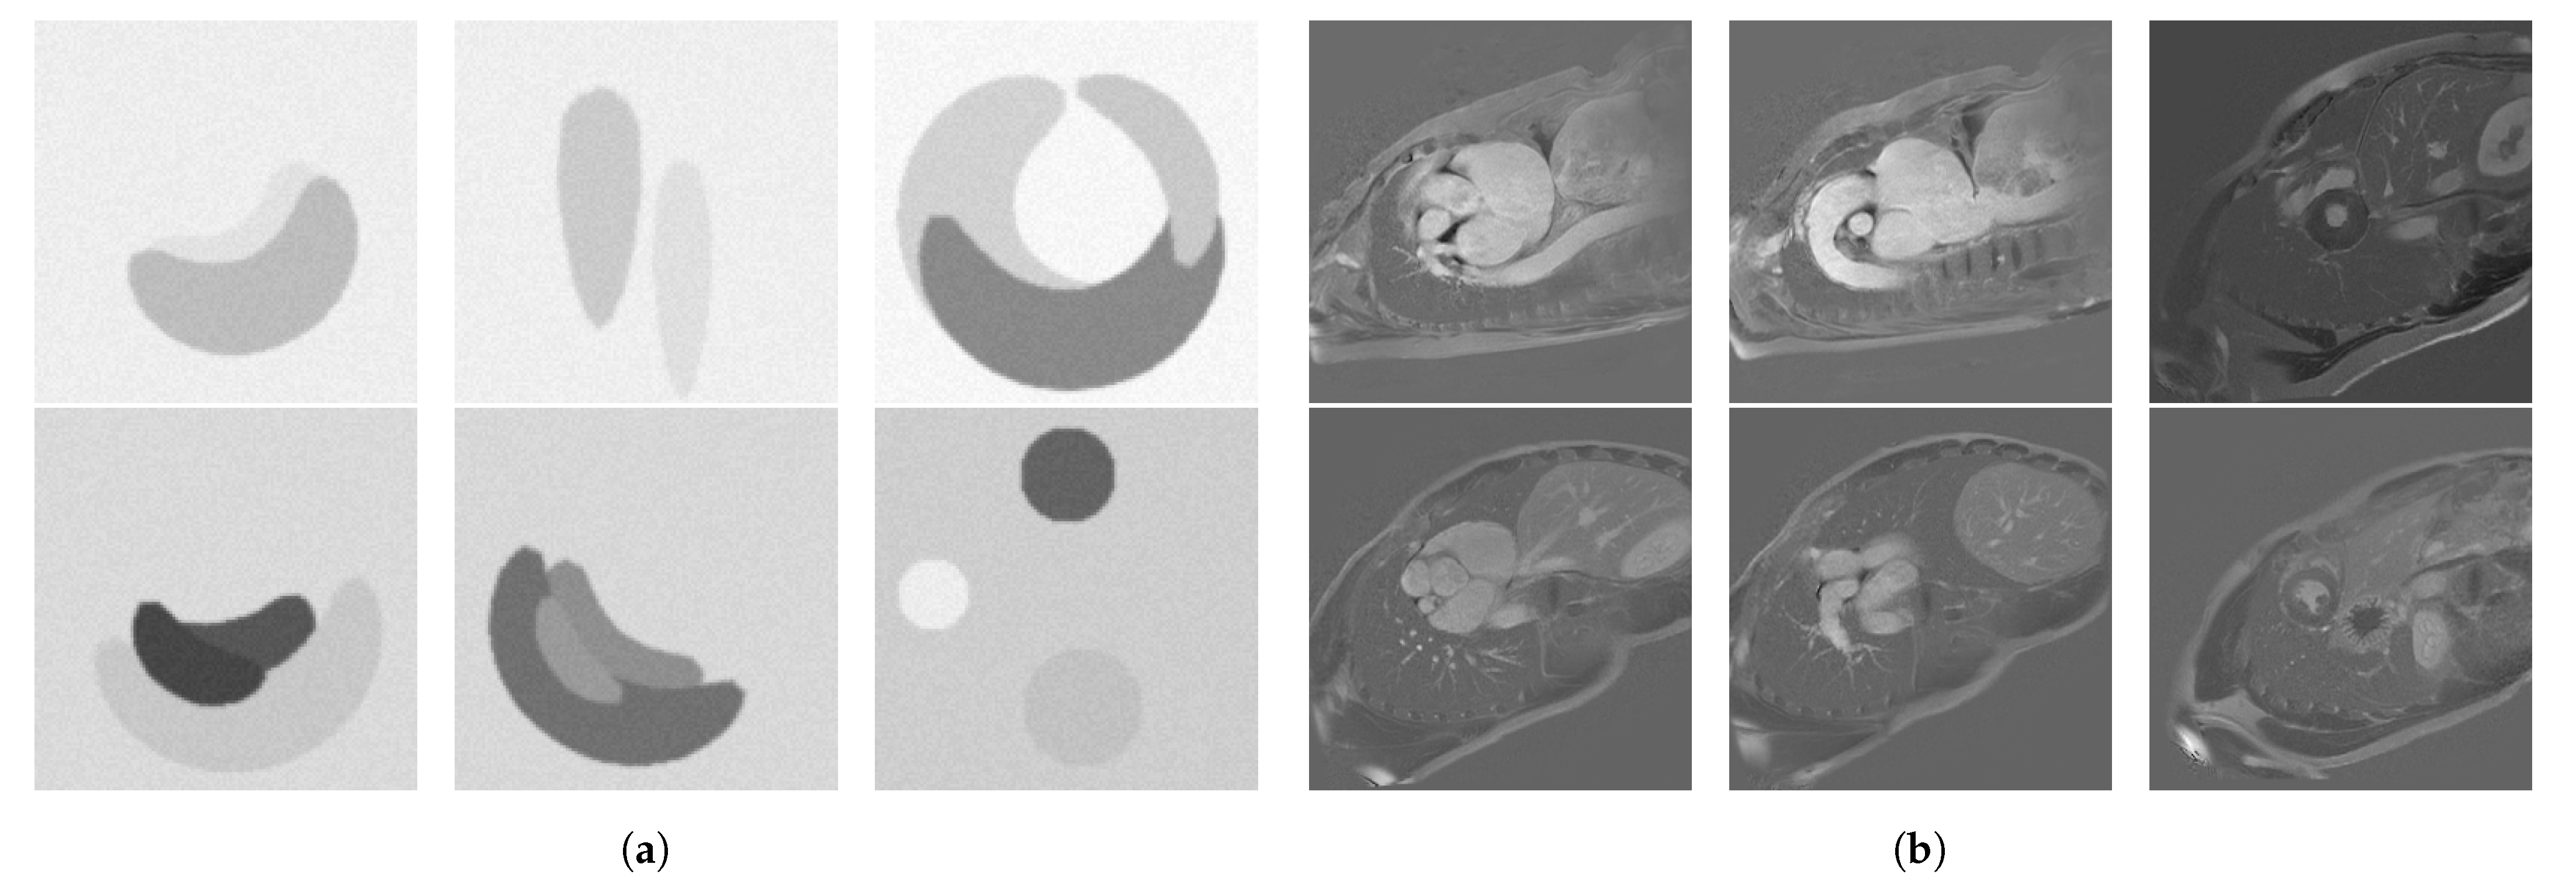

3.2.1. Comparing , and

3.2.4. Impact of Batch Size over the Optimization Process

3.2.5. Evaluating the Difficulty of Edge Detection with Respect to Batch Size

4.1. Robustness Analysis

4.1.1. Comparing , , and

4.2. Optimization Analysis

4.2.1. Impact of Batch Size over the Optimization Process

4.2.2. Evaluating the Difficulty of Edge Detection with Respect to Batch Size